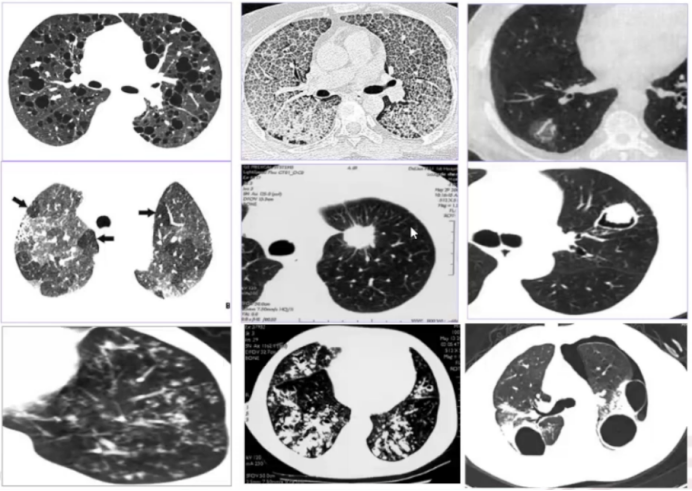

入院后胸片及胸部CT显示:右上肺、右中肺及左下肺可见磨玻璃影;右下肺存在大片实变影,但肺容积基本正常,仅轻度缩小,提示病变可能为慢性或亚急性过程(急性重症感染常伴随肺容积明显缩小);病灶内可见支气管充气征,支气管形态异常——未呈现正常的“由粗变细”趋势,反而局部扩张、僵直,形成“枯枝征”;此外还可见“青枝征”(支气管形态正常,结构清晰)(图2)

图片

2  “枯枝征”和“青枝征”表现

“枯枝征”形成的主要机制是牵拉作用,常见于机化、肿瘤等情况。具体而言,当存在支气管周围结构发生病变时,如伴行的动脉、淋巴及间质,或支气管周围的肺泡发生病变时,尤其当这些病灶发生机化或出现肿瘤时,会对支气管形成牵拉作用导致其扩张,形成“枯枝征”。